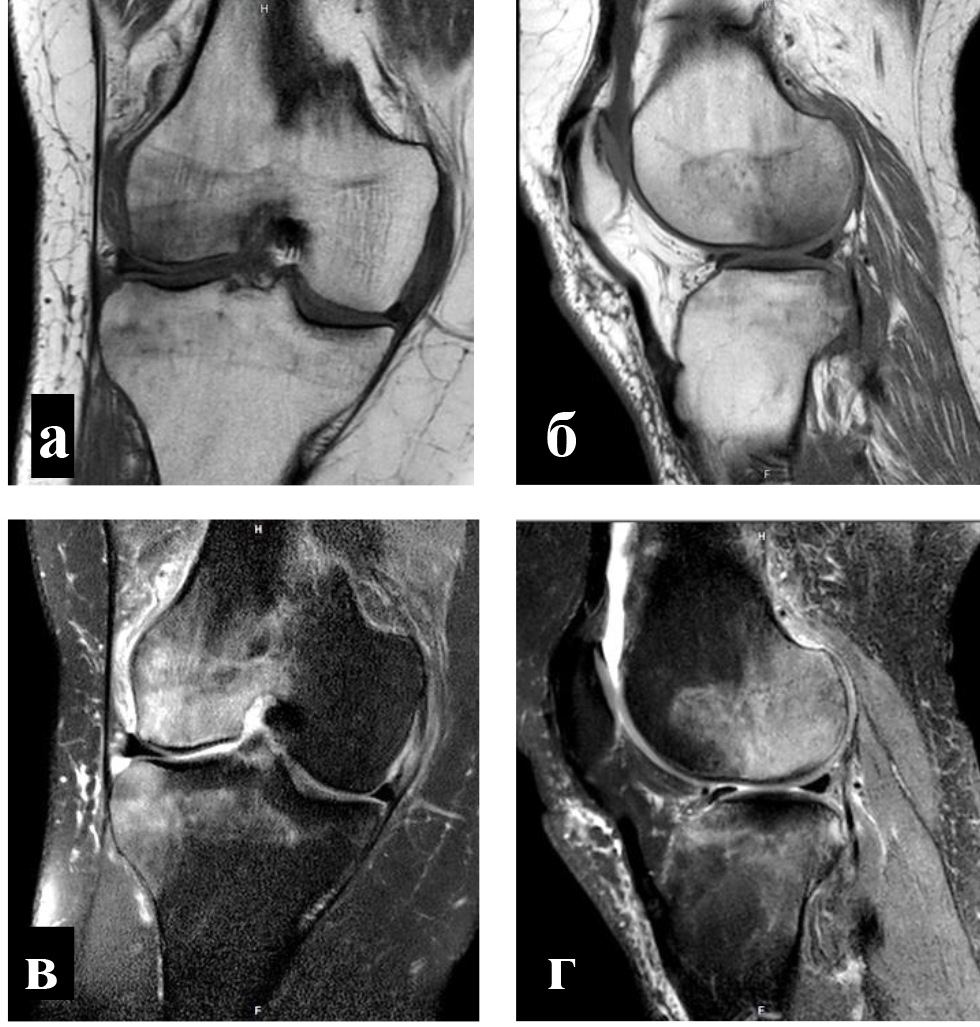

Для определения локализации и распространенности перегрузочного отека костного мозга всем пациентам выполняли МРТ. На Т1-взвешенных изображениях визуализировали снижение интенсивности сигнала, на Т2-взвешенных изображениях с жироподавлением и на коротких последовательностях «восстановления – инверсии» (STIR) выявляли высокую интенсивность сигнала (рис. 1).